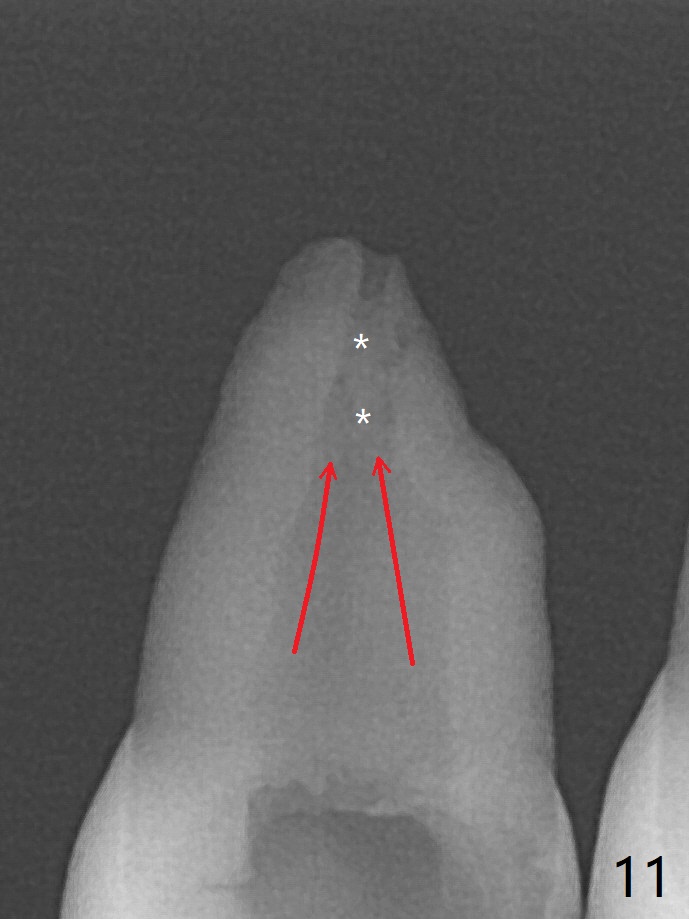

A 14-year-old woman with crowding returns to clinic for extraction of the 1st bicuspids. Orthodontic treatment has started partially. Because of severe caries at UR5 (Fig.1 *), BWs and PA are taken, which reveal DO incipient caries at UL, LL5 (Fig.2) and large PARL at UR5 (Fig.3 *). Upon receiving a revised treatment plan, four of 2nd bicuspids are extracted. The large PARL is confirmed intraop. Examination of the extracted teeth shows mesial caries at UL5, which is not detected by X-ray (Fig.4 <). By comparison, DL caries of UL5 is more severe (Fig.5). Check the neighboring teeth for caries when the patient returns for recall. The pulpal exposure of UR5 is large (Fig.6). So is the pulpal chamber (Fig.7). The large canal (Fig.7) in fact consists of 2 ones (Fig.11 red arrows) with a separation in between (*). The DL caries at LL5 is at the stage of decalcification (Fig.8), not visible in X-ray (Fig.12, as compared to Fig.7 >).